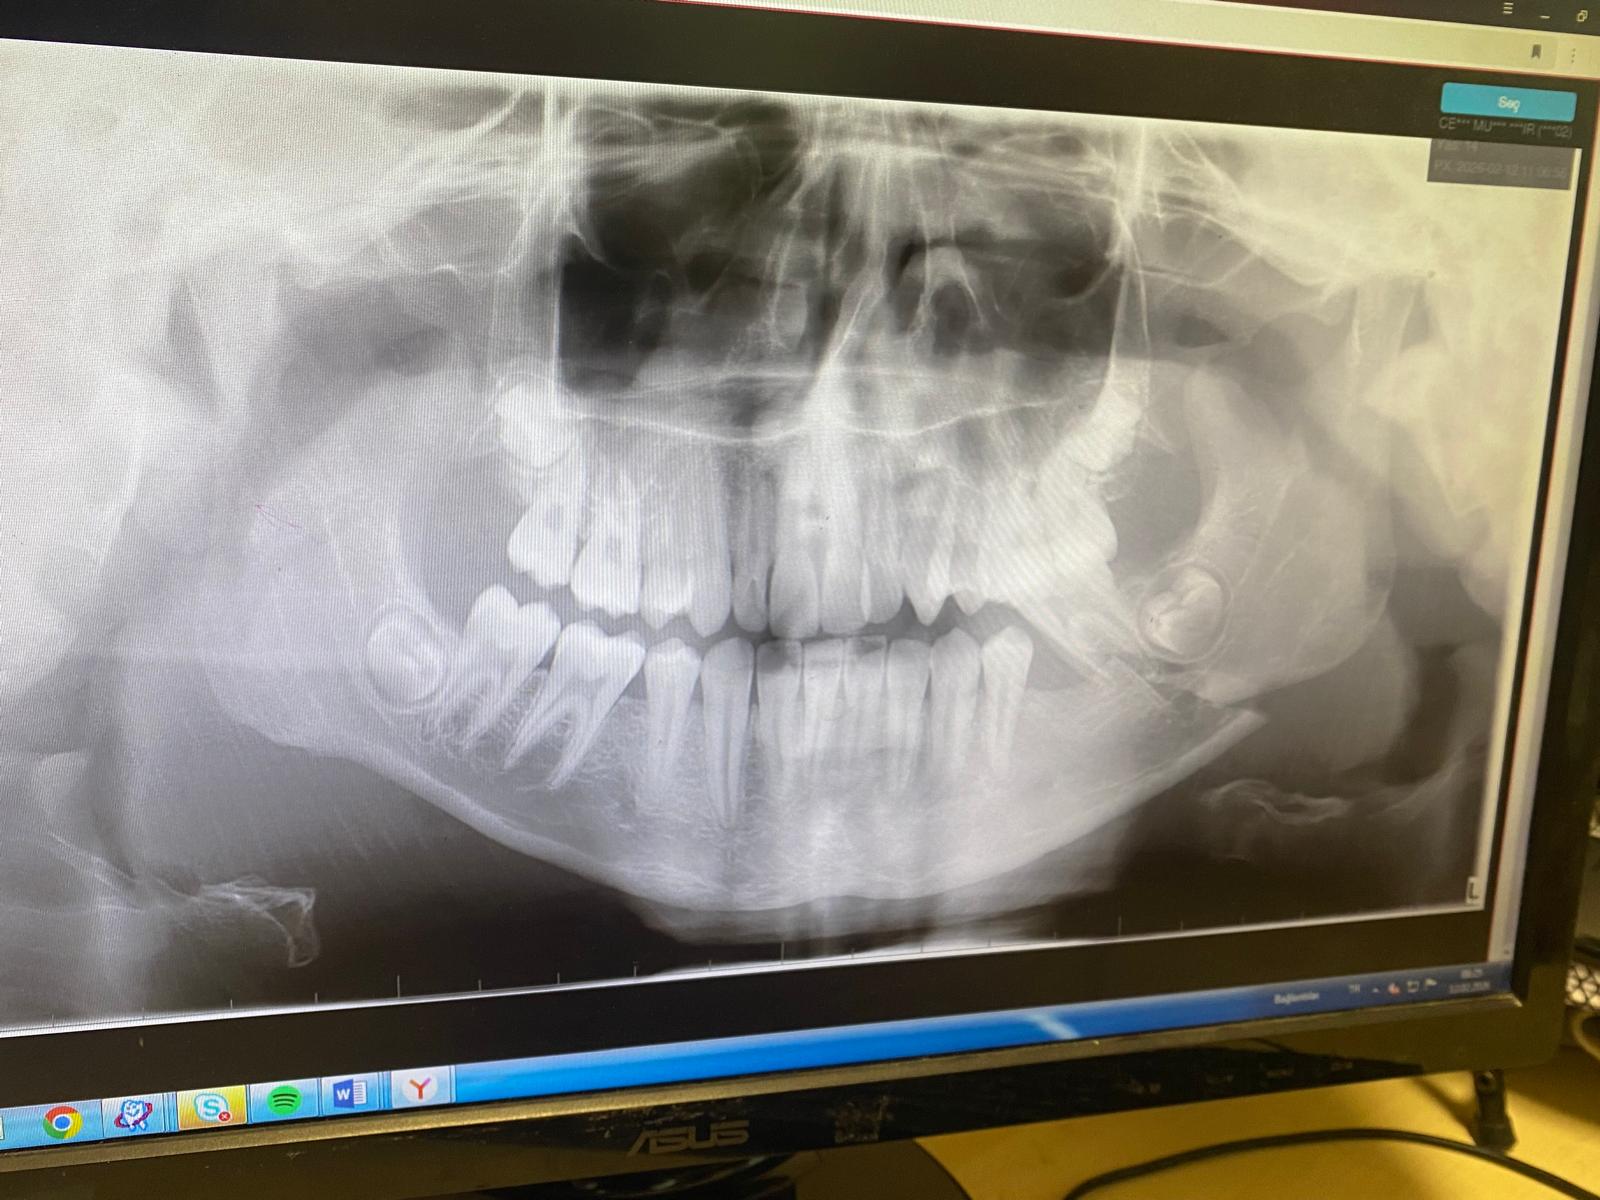

Olay, geçtiğimiz Çarşamba sabahı Antalya Ticaret Borsası Mesleki ve Teknik Anadolu Lisesi’nde yaşandı. İddiaya göre, 14 yaşındaki 9. sınıf öğrencisi Muhammet Yasir Ç., üç öğrencinin sözlü tacizine uğradı. Tartışma, öğrencilerden Ö.C.K.’nin "Bana niye ters bakıyorsun?" diyerek fiziki saldırıya geçmesiyle şiddete dönüştü. Aldığı darbelerle ağır yaralanan talihsiz gencin, Akdeniz Üniversitesi Hastanesi’nde yapılan kontrollerinde çenesinin iki ayrı noktadan kırıldığı tespit edildi. 16 Şubat’ta ameliyata alınan Muhammet Yasir, 5 saat süren operasyonla çenesine plak ve vidalar takılarak tedavi altına alındı. Doktorlar, öğrencinin iyileşme sürecinin en az 6 ay süreceğini belirtti.